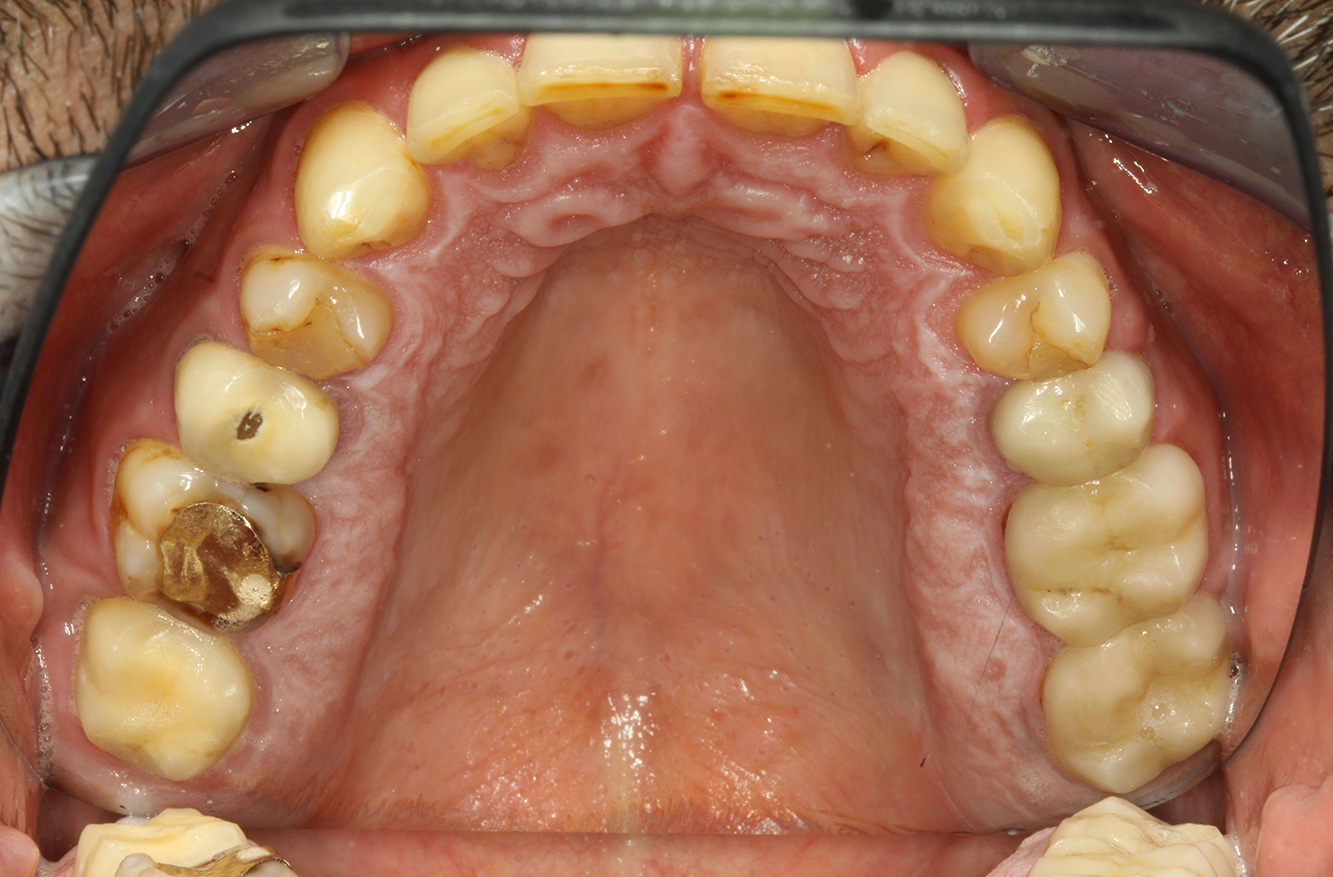

The endocarditis patient with active caries lesions*

The patient is 39 years old and has previously undergone aortic valve replacement due to valve failure and endocarditis. ASS 100 is taken regularly as an anticoagulant. In terms of lifestyle, the patient’s diet is classified as caries-promoting due to the regular consumption of sugary foods and the fact that six to seven meals are consumed daily. The patient’s oral health indicates a moderate risk of caries, with active lesions. The risk of periodontitis is low, but gingivitis is present. The following recommendations are made for prophylactic treatment.

Enough time must be allowed for the instructive/ motivational discussion. The negative impact of nutritional behaviour on oral health (9) should be clearly conveyed to the patient. With regard to the history of endocarditis, the connections between cariogenic bacteria and cardiovascular disease may also be discussed (12). This can strengthen the patient’s motivation to make a sustainable change to their diet. The discussion should convey to the patient the importance of – and motivate them to practise – good oral hygiene at home.

Fluoridation is recommended to further support the prevention of caries, and especially to prevent new formation around the restoration edges, and to seal the root surfaces. Both of these measures can reduce the teeth’s sensitivity to temperature.